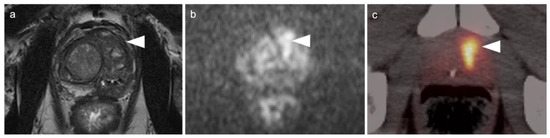

- Maruyama, S.; Sato, Y.; Satake, Y.; Mise, H.; Kim, T. Diffusion-Weighted MRI and FDG-PET in Diagnosis of Endometrial Stromal Nodule. Case Rep. Obstet. Gynecol. 2015, 2015, 540283. [Google Scholar] [CrossRef][Green Version]